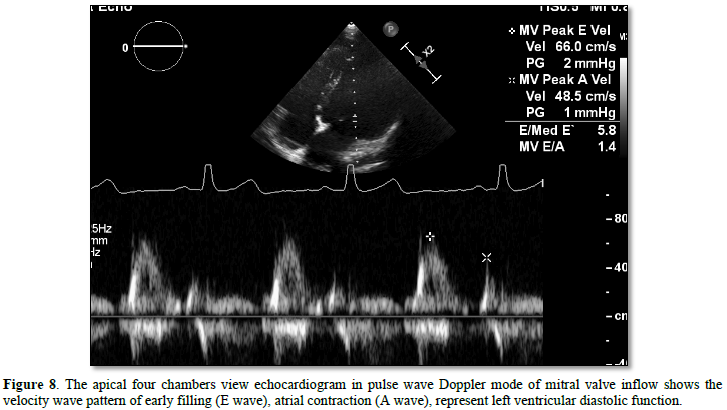

The reason for coronary artery relocalization procedure has influence to the coronary supply and regional wall motion of LV Although the main of pumping was the left sided ventricle (after repair). But in several cases the morphology of main ventricle was more trabeculation or noncompacted. This point was considered evidence of reducing ventricular pumping and related to impair ventricular function. The left ventricular ejection fraction (normal LVEF > 55%) in systolic function, the circumferential or longitudinal strain was important parameter for described neo-left ventricular function [10]. (Normal global longitudinal strain -15% to -22%) [19]. After some report use -20% cut off point for considering normal [20]. However, the right ventricular function was also necessary, in addition the tricuspid annulus plane exertion which is a parameter for evaluating RV function and many cut points in several main diseases such as in pulmonary hypertension if TAPSE < 1.6 cm. (since 1.5 cm. below) It’s being able to detect elevated pulmonary pressure in patients with interstitial lung disease who underwent cardiac catheterization [21]. (Accept rang > 1.5 cm.) There is also tissue Doppler velocity of S' wave at lateral wall beside leaflet of the tricuspid valve that can be a parameter used to evaluate RV function. (Normal > 11.5 cm/s) [22]. About the diastolic function E/E’ at mitral valve inflow able to reflect the filling pressure of LV and LA contraction. The peak velocity of E wave of mitral valve inflow by pulse wave Doppler (Figures 5-8) and the peak velocity of E’ wave of tissue pulse wave Doppler able to ratio E/E’ if greater than 15 may be related to elevate left atrial pressure, such as mitral stenosis or regurgitation and pulmonary vein stenosis or pulmonary hypertension. (Normal < 15) [23].